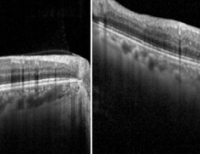

- GLP-1 수용체 작용제 비만약, 녹내장 발병·치료에 영향 줄 수 있을까?

- 엠브레인 트렌드모니터가 전국 만 19~59세 남녀 1000명을 대상으로 ‘다이어트 경험 및 비만치료제 관련 인식 조사’를 진행한 결과 약 44.4%가 비만치료제...